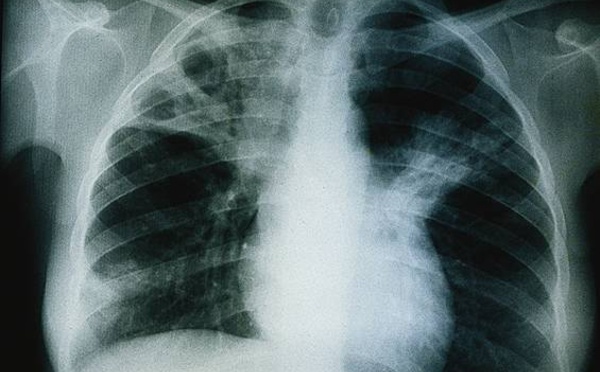

La tuberculose est la maladie infectieuse la plus meurtrière au monde. Au Sénégal, 13 166 cas, toutes formes confondues, ont été enregistrés en 2016. Selon les chiffres du ministère de la Santé, le...

La région de Dakar concentre 45 pour cent de la totalité des cas de tuberculose recensés au niveau national, a fait savoir mercredi la coordinatrice du Programme national de lutte contre la...